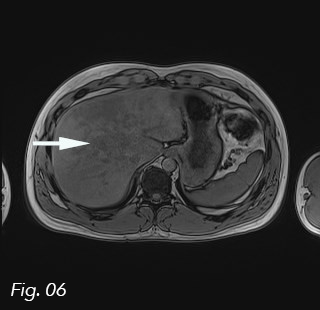

Fig. 6: Axial T1 out-of-phase image. Signal drop in the fatty infiltration (arrow).

The portal vein and hepatic artery had normal Doppler signals and there was no invasion of the vessels (Fig. 3). Normally, a contrast-enhanced ultrasound (CEUS) would have been performed, but due to the large size, the irregular borders and the patient’s comorbidities, an MRI of the abdomen with liver specific contrast agent (Primovist) was performed to characterize it further. In- and out-of-phase images showed that the lesion was focal fatty infiltration, but with an unusual large size (Fig. 4, 5, 6). The behavior of the lesion after contrast administration was similar to the surrounding liver parenchyma.